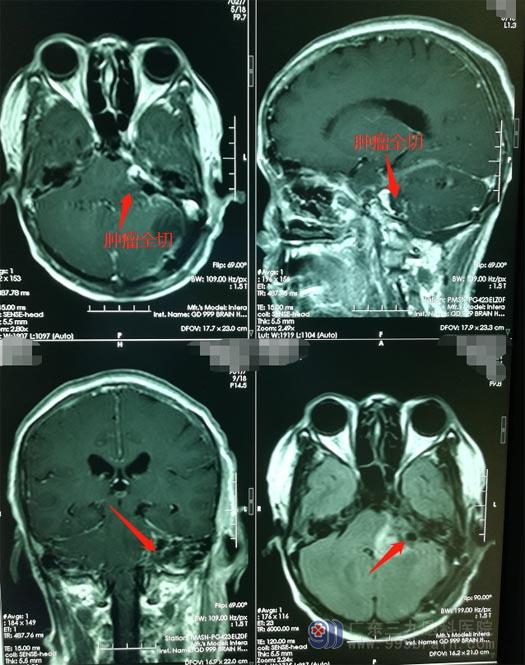

医院副院长、神经外五科主任鲁明带领治疗团队慎重地术前讨论后,由鲁明主刀为徐阿姨行“左侧桥小脑角占位切除术”,术中见肿瘤位于左侧桥小脑角区,血供丰富,肿瘤与面神经粘连,术中采用电刺激辨认面神经,保护了面、听神经功能,显微镜下分块将肿瘤全部切除,术程顺利。

康复出院时,徐阿姨高兴说:“耳鸣没有了,也听得见了。”